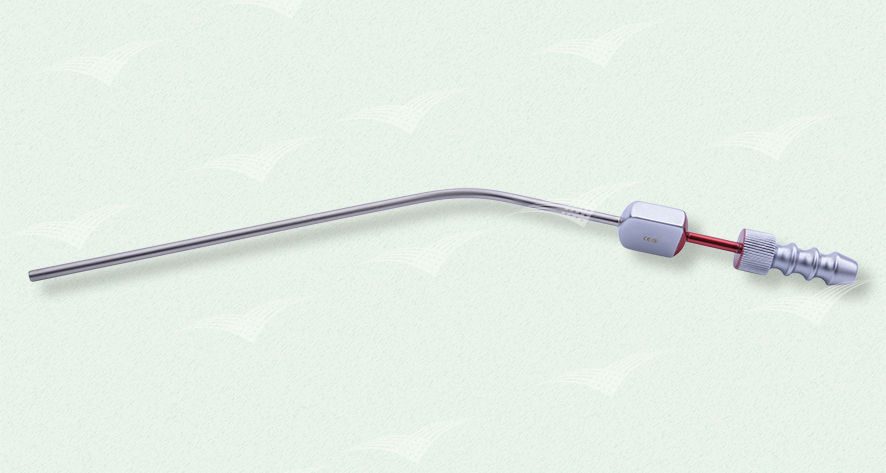

Frazier Sauger

einzeln steril verpackt, Einweg Metallinstrument

Artikelnummer: n. v.

Kategorien: Einweg-Produkte, Metallinstrument